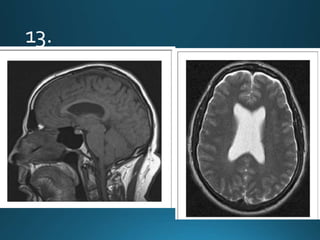

Adrenoleukodystrophy (ALD) is a x-linked inherited metabolic peroxisomal

disorder characterised by lack of oxidation of very long chain fatty acids

(VLCFAs) that results in severe inflammatory demyelination of the

periventricular deep white matter with posterior-predominant pattern and early

involvement of the splenium of the corpus callosum and periatrial white matter

changes

MRI

A majority of cases tend to show symmetrical cerebral white matter signal change involving

the posterior (occipitoparietal) periventricular white matter (i.e. posterior cerebral, around

splenium and peritrigonal white matter).

Signal intensity

T1

central zone: hypo-intense

T2

central zone: markedly hyperintense

intermediate zone: isointense to hypointense

peripheral zone: moderately hypointense